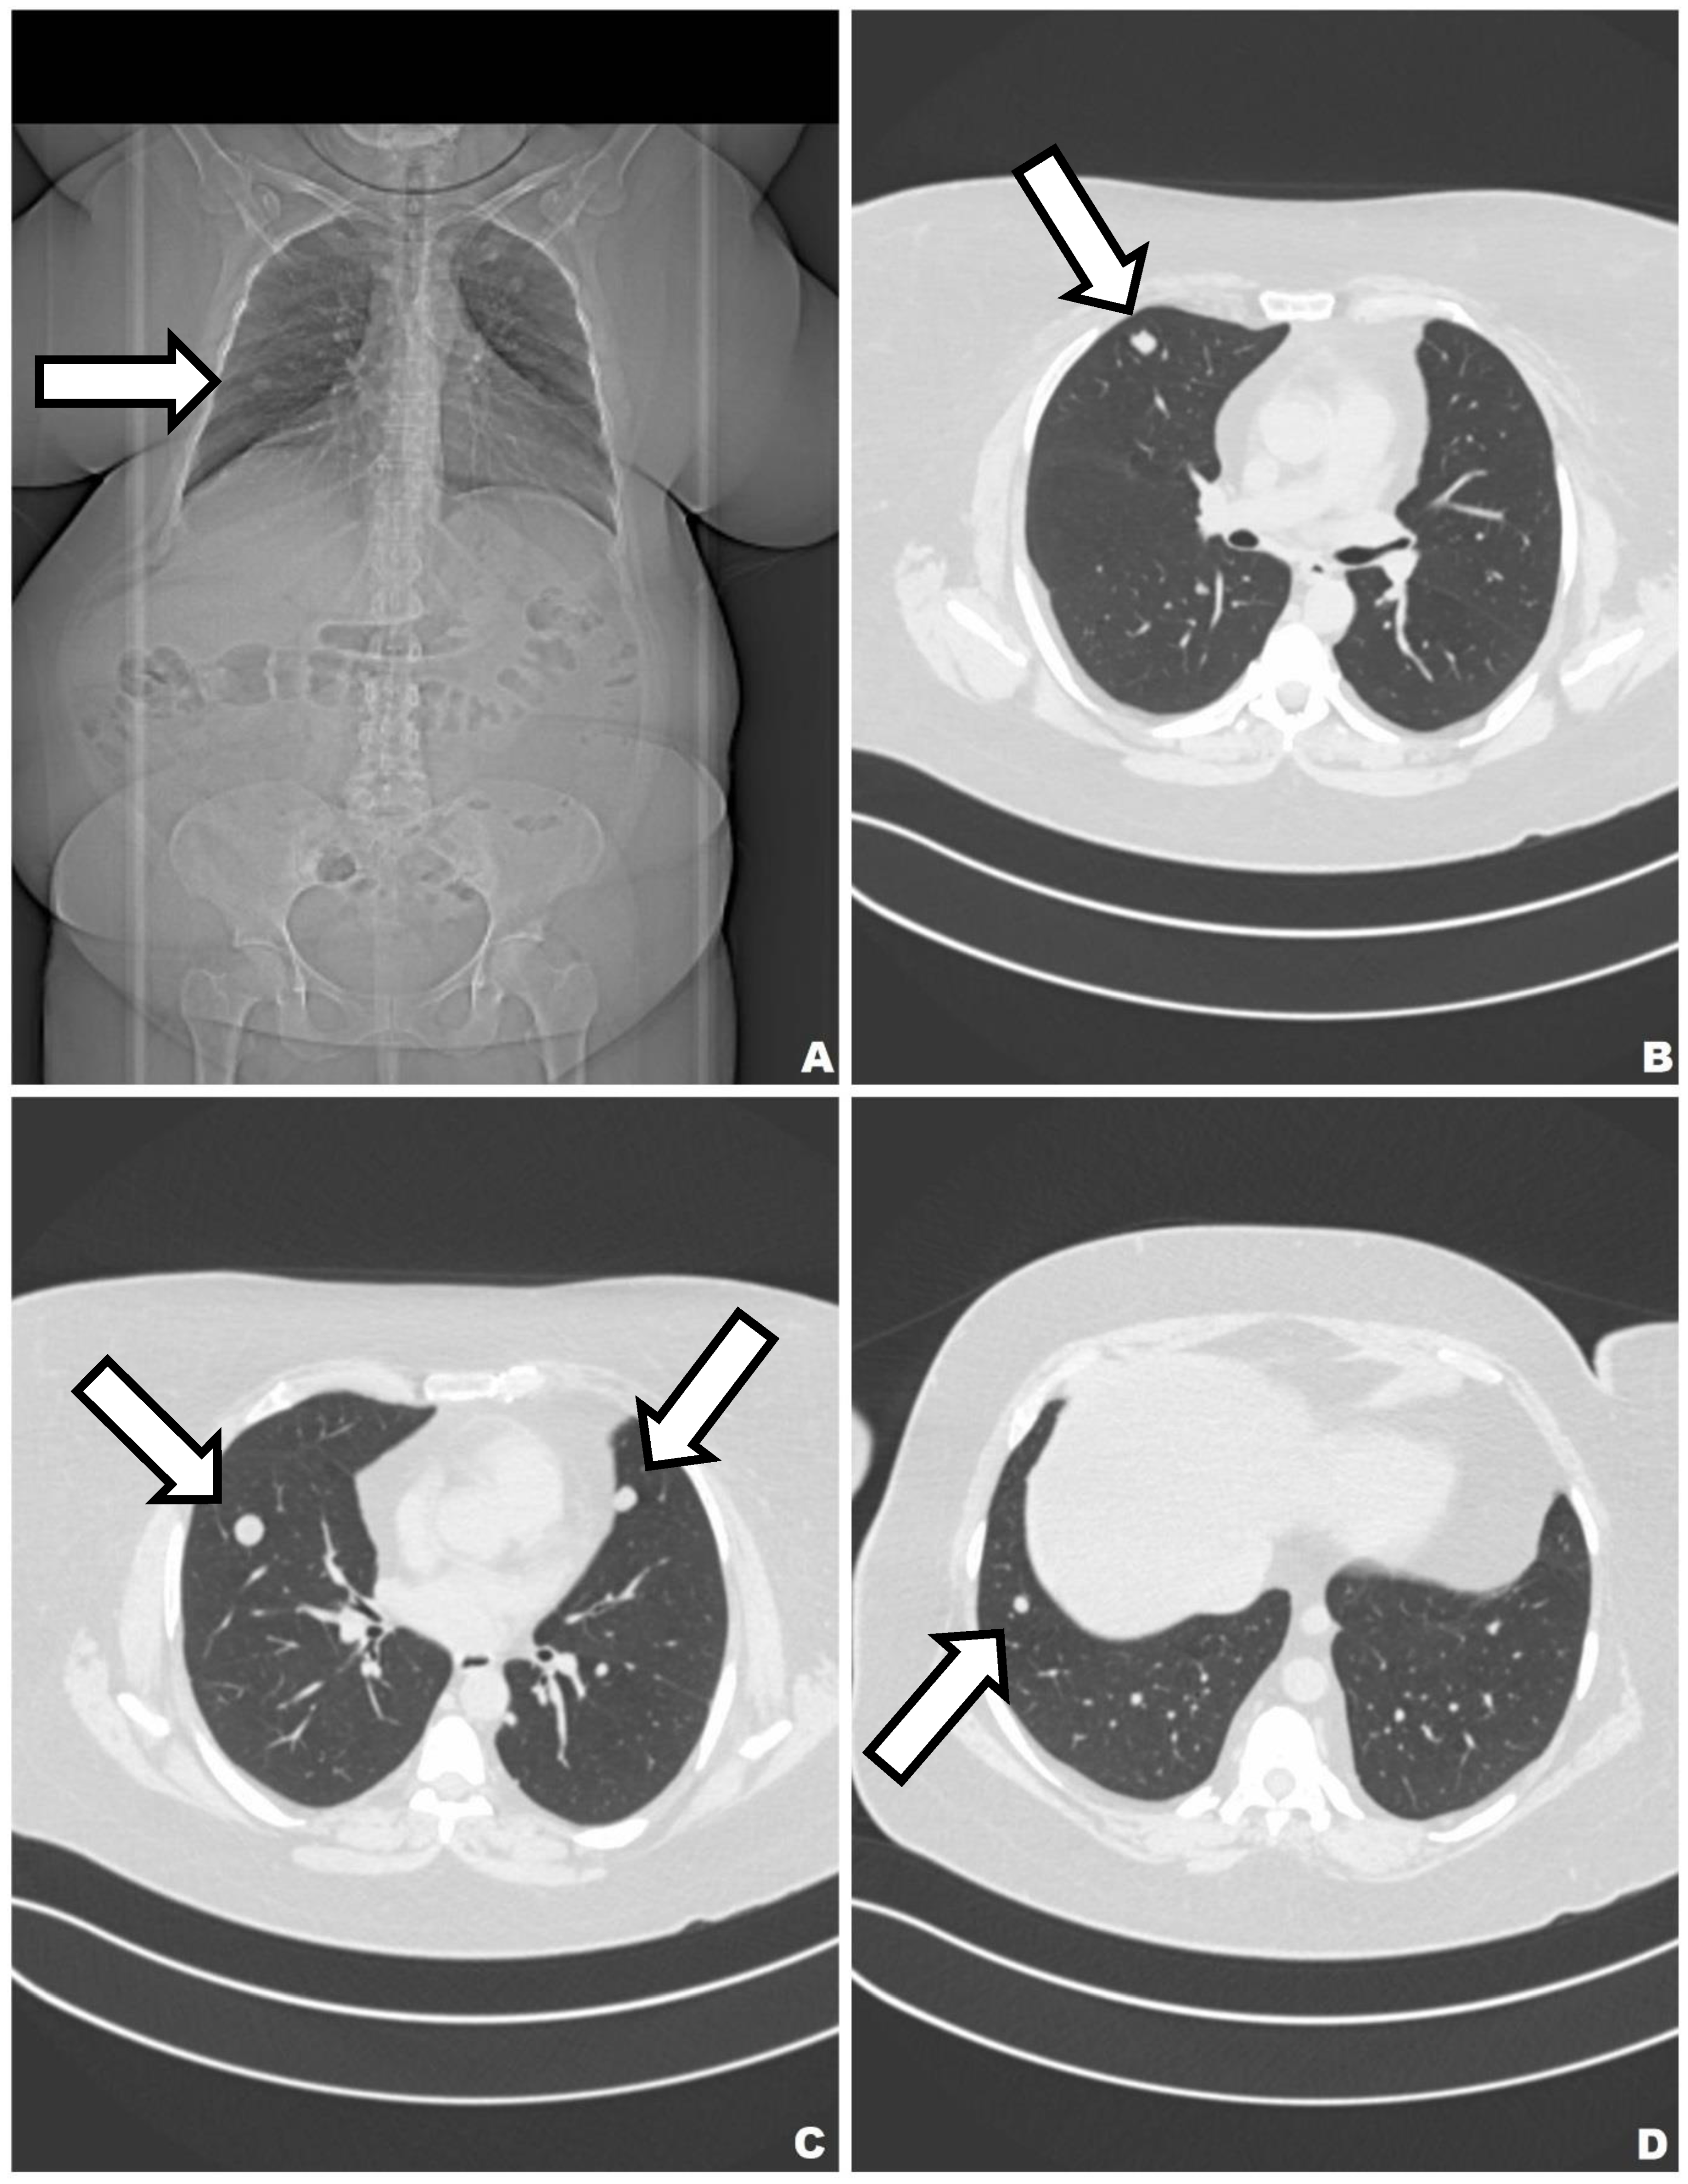

2. Case 1

3. Case 2

4. Case 3